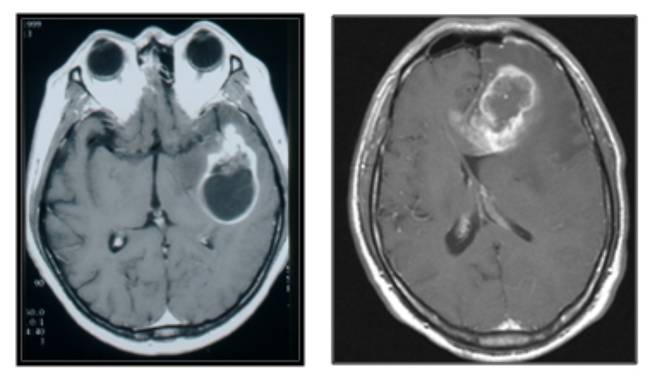

뇌종양은 조직학적 특성에 따라 '양성'과 '악성'으로 나눈다. '양성 뇌종양'은 성장 속도가 1년에 2㎜ 미만으로 느리다. 주변 부위와 비교적 명확히 구분되기 때문에 수술을 통한 완치 가능성도 높다. 종양의 크기·위치에 따라 일상생활이 불편할 수 있어도, 5년 생존율이 90% 이상일 만큼 생명에 거의 지장이 없다. 따라서 별다른 증상이 없는 경우 경과 관찰만 하며, 증상이 있거나 주기적으로 MRI(자기공명영상)를 촬영하며 관찰하다가 성장 속도가 일반적인 경우보다 빠르다고 판단될 때 치료를 고려해도 늦지 않다.

'악성 뇌종양'은 진행이 빠르고, 성장하면서 뇌 조직을 침범하는 경향을 보인다. 뇌교종이 대표적이다. 뇌교종은 뇌신경세포를 지지하는 교세포에서 발생하며, 절반 이상이 악성이다. 양성 뇌교종도 시간이 지나면서 악성화되는 경우가 많다. 뇌교종이 발견되면 일부 예외적인 경우를 제외하고, 대부분 증상이 없더라도 치료가 필수적이다.